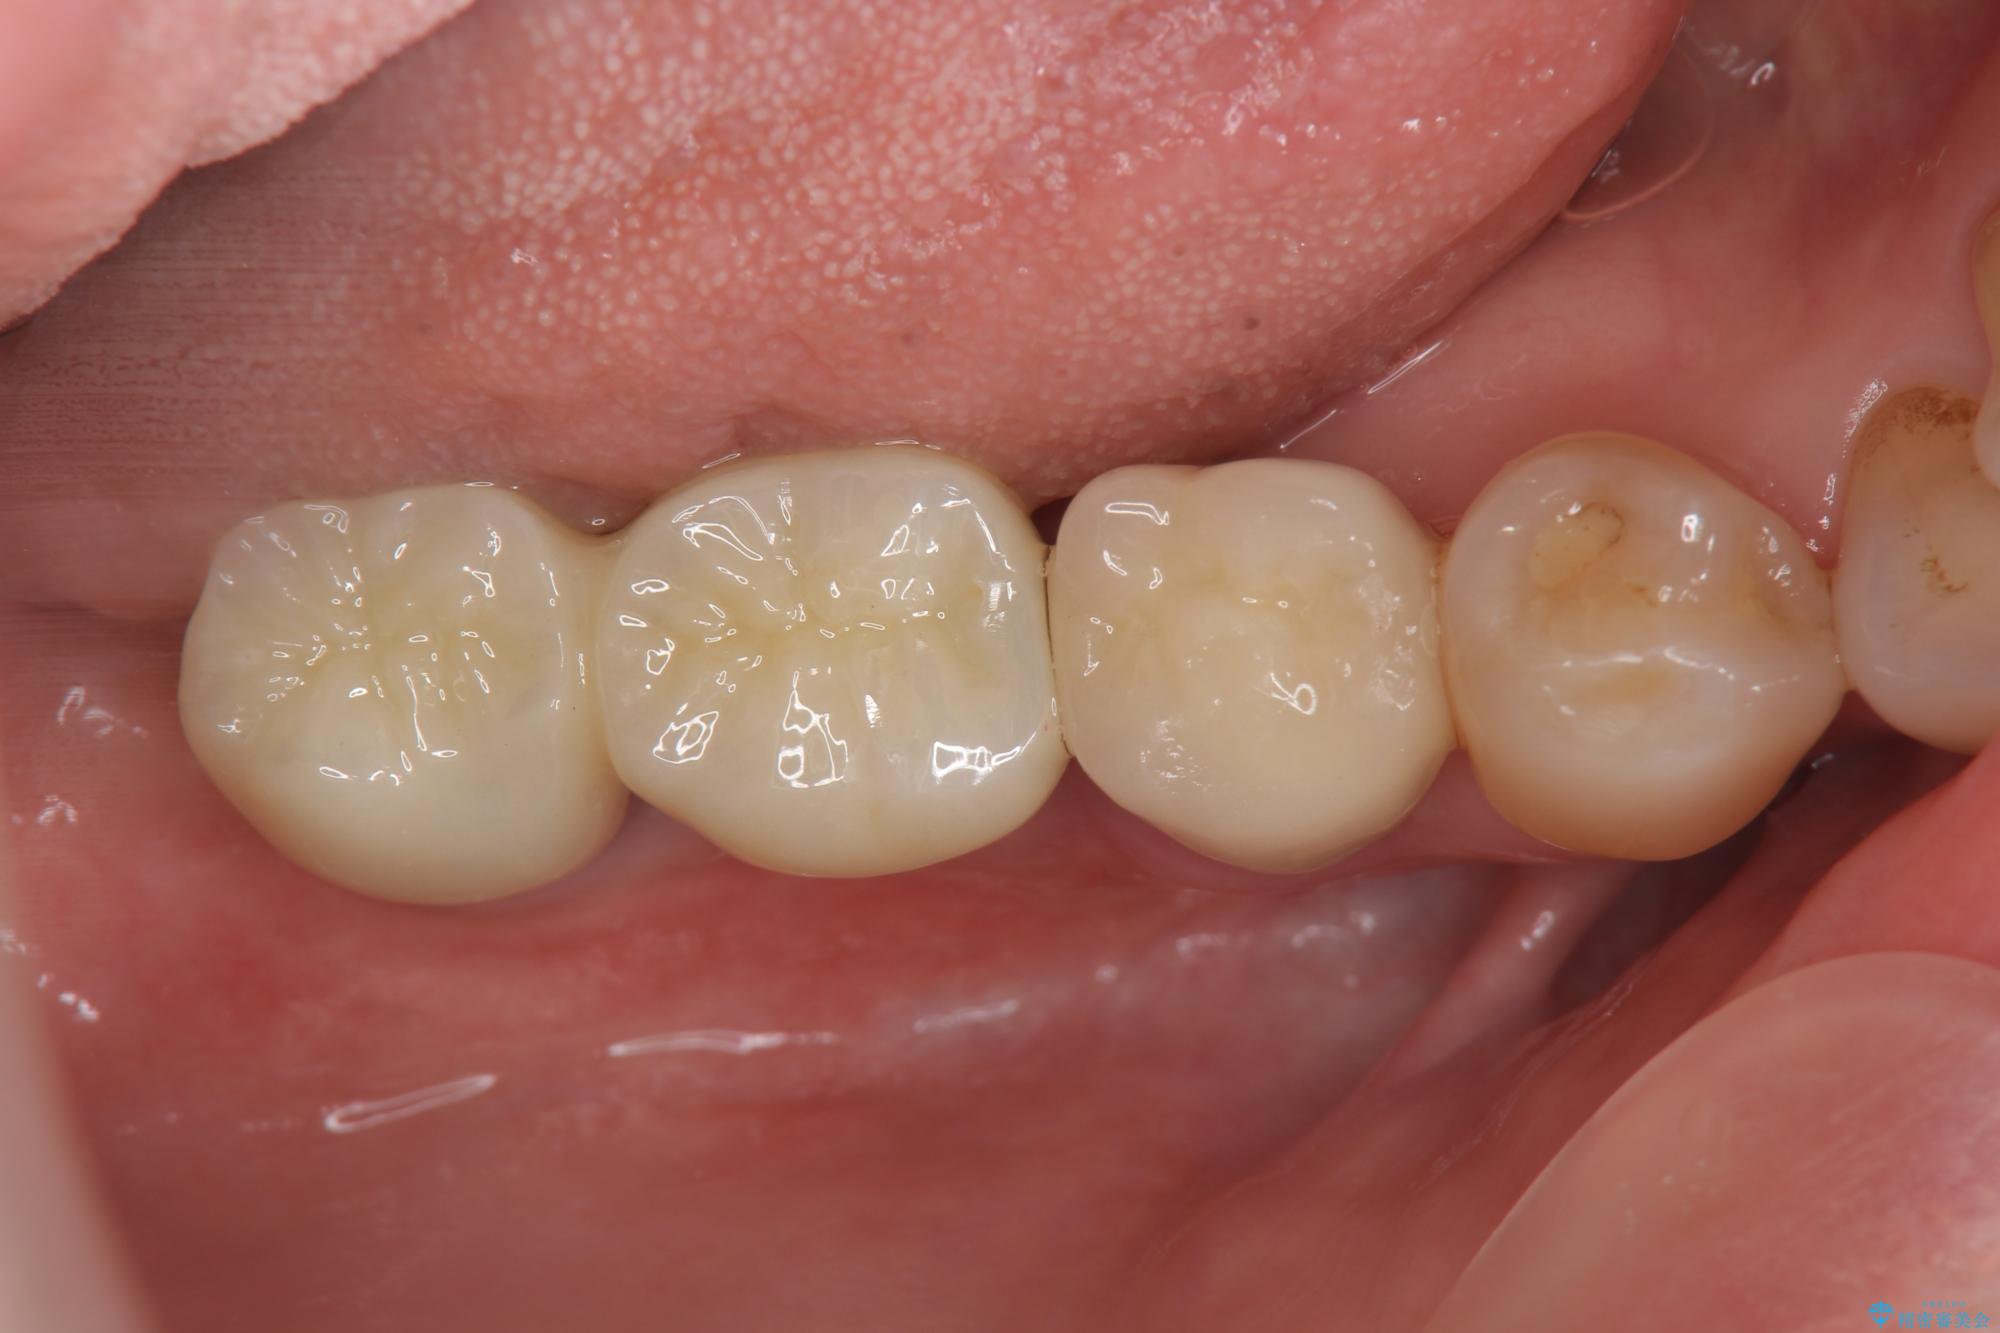

治療後

奥歯から膿のにおいがする インプラントによる機能回復 治療後画像 奥歯から膿のにおいがする インプラントによる機能回復 治療後画像 奥歯から膿のにおいがする インプラントによる機能回復 治療後画像 奥歯から膿のにおいがする インプラントによる機能回復 治療後画像

治療を終えて

歯は大きな力がかかると割れてしまうことがよくあります。

破折した歯はほとんどの場合抜歯が必要になることが多く、インプラントを用いた咬合機能の回復は、また噛めるようになるだけでなく残っているその他の歯を守る意味でも非常に大きな意味を持ちます。